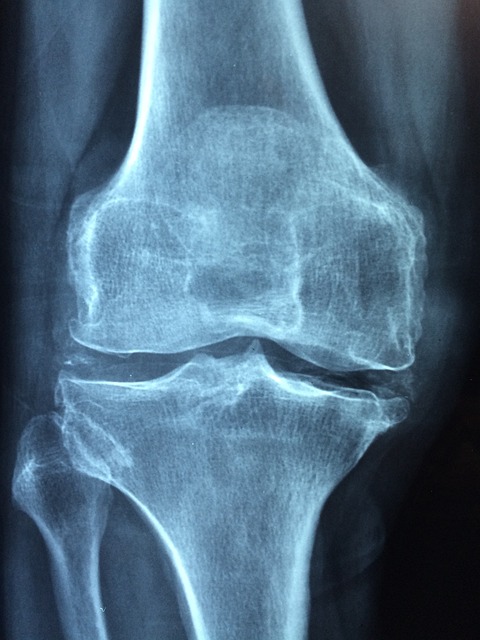

노화에 따라 관절 연골이 닳고 뼈끼리 마찰되면서 염증과 통증이 생긴다. 특히 무릎, 고관절, 손가락 등 사용이 많은 부위에서 흔하다.

5. 체중 증가

과체중은 특히 무릎과 고관절에 큰 부담을 주어 관절 손상을 가속화시킨다.

- 관절이 움직일 때마다 소리(크레피투스)가 나고 아프면 연골 마모 가능성 있음